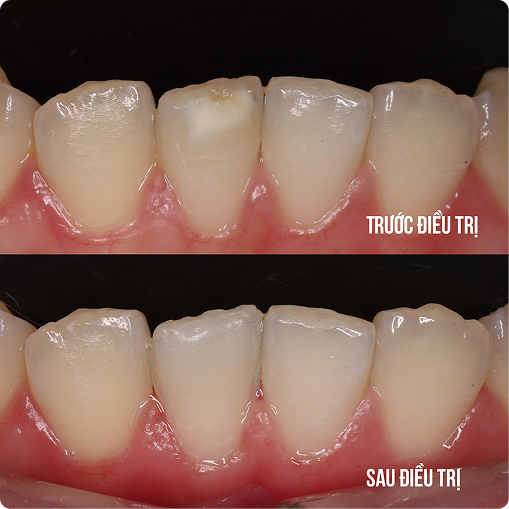

During this stage, parents should closely monitor their child’s tooth replacement process and schedule regular dental check-ups. This helps detect common abnormalities early, such as missing tooth buds, extra teeth in the midline gap, or impacted teeth (mesiodens), which can obstruct tooth eruption and affect the positioning of the remaining teeth.